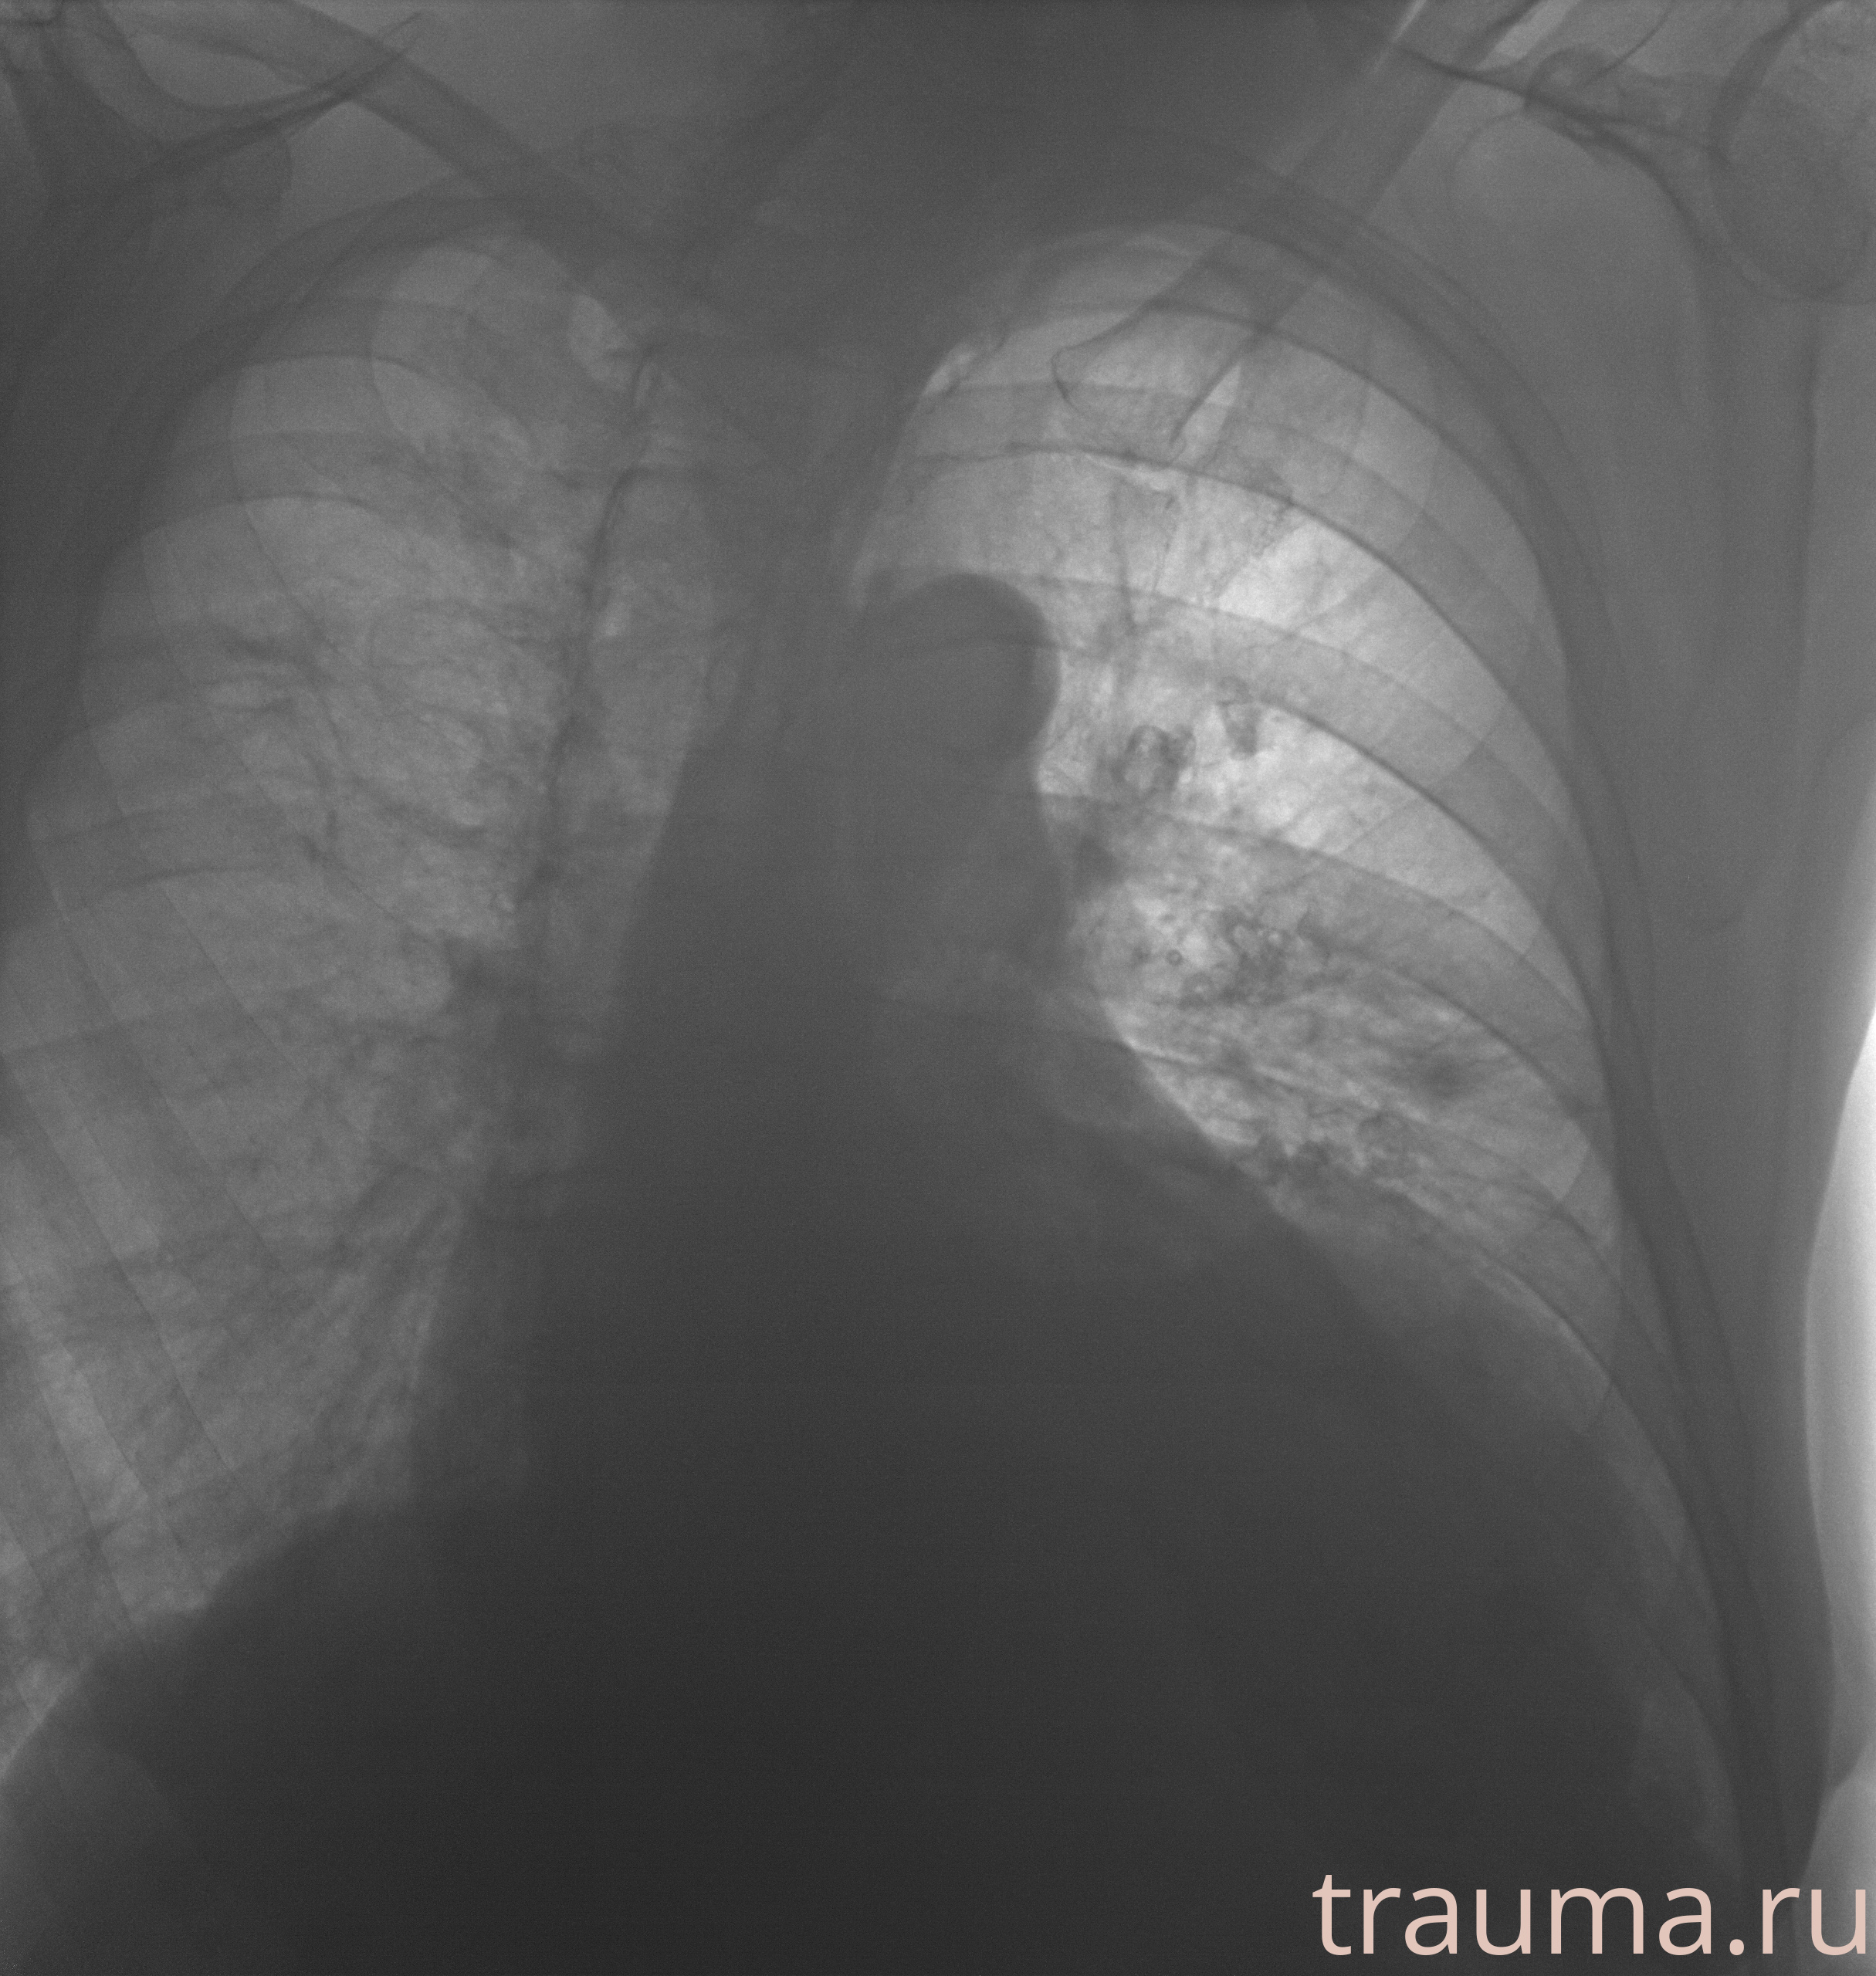

Рентгенограммы

Рентген на дому: по вашему адресу приезжает врач-рентгенолог, травматолог-ортопед с мобильным рентгеновским аппаратом, проводит диагностику травмы или заболевания, делает необходимые рентгенограммы, дает рекомендации по дальнейшему лечению. Получить качественные снимки в домашних условиях возможно благодаря уникальной методике, разработанной МосРентген Центром для института  Склифосовского

при переломе шейки бедра и пневмонии от компании МосРентген Центр - партнера Института имени Склифосовского